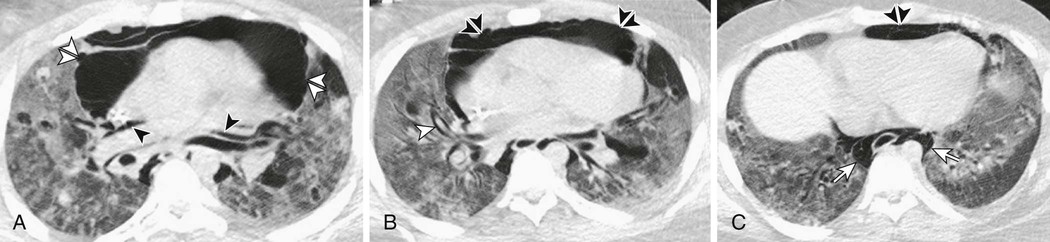

Although mechanical ventilation for ARDS may be lifesaving, there is abundant preclinical and clinical evidence that it can also be harmful.106,106a While it was quickly recognized that excessive airway pressure could lead to barotrauma (Fig. 100-4), including pneumothorax, pneumomediastinum and subcutaneous emphysema, attention has since turned to subtler but more common manifestations of lung injury related to mechanical ventilation. Mechanical ventilation can induce pulmonary edema by causing increases in both epithelial and endothelial permeability.106 Indeed 40 years ago Webb and Tierney demonstrated that ventilation of rats with high peak airway pressures could lead to severe pulmonary edema,107 and more than 20 years ago, investigators noted that mechanical ventilation could produce a form of increased permeability pulmonary edema remarkably similar to ARDS.108 Now, the accumulated evidence suggests that certain mechanical ventilation strategies may aggravate if not induce ARDS in some patients.109

It is important to point out that patients with ARDS may be especially vulnerable to VILI because of the heterogeneous nature of the pulmonary parenchymal injury. On computed tomography scans of the lungs, normal-appearing lung and densely consolidated injured lung are both seen; as a consequence, there are marked regional differences in lung compliance113 (Fig. 100-5). A tidal volume designed to inflate an entire lung would preferentially inflate the normal-appearing areas, potentially leading to overdistention and volutrauma. Patients with ARDS may similarly be more vulnerable to atelectrauma. Although some evidence suggests that normal lungs can tolerate at least short periods of cyclic opening and closing of airways from mechanical ventilation,114 injured lungs, such as in ARDS, would be exposed to much higher shear stresses and would not be expected to fare as well.115

Another feared complication of ARDS is barotrauma (pneumothorax, pneumomediastinum, subcutaneous emphysema, eFig. 100-1) due to the effect of positive pressure ventilation in heterogeneous lungs with diminished compliance. Because most patients with ARDS will be supine (rather than erect), diagnosing a pneumothorax requires vigilance; the radiographic appearance of a pneumothorax is different and can be subtler in the supine patient (e.g., air in the costophrenic angle, the “deep sulcus” sign). Data from a number of prospective studies suggest that the incidence of barotrauma in ARDS currently is about 10% or less.109,159,160